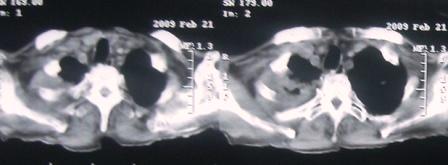

xx 男 63岁 发热 家属描述有时高热 有时低热 抗酸杆菌阴性 于2月21号 胸片及ct